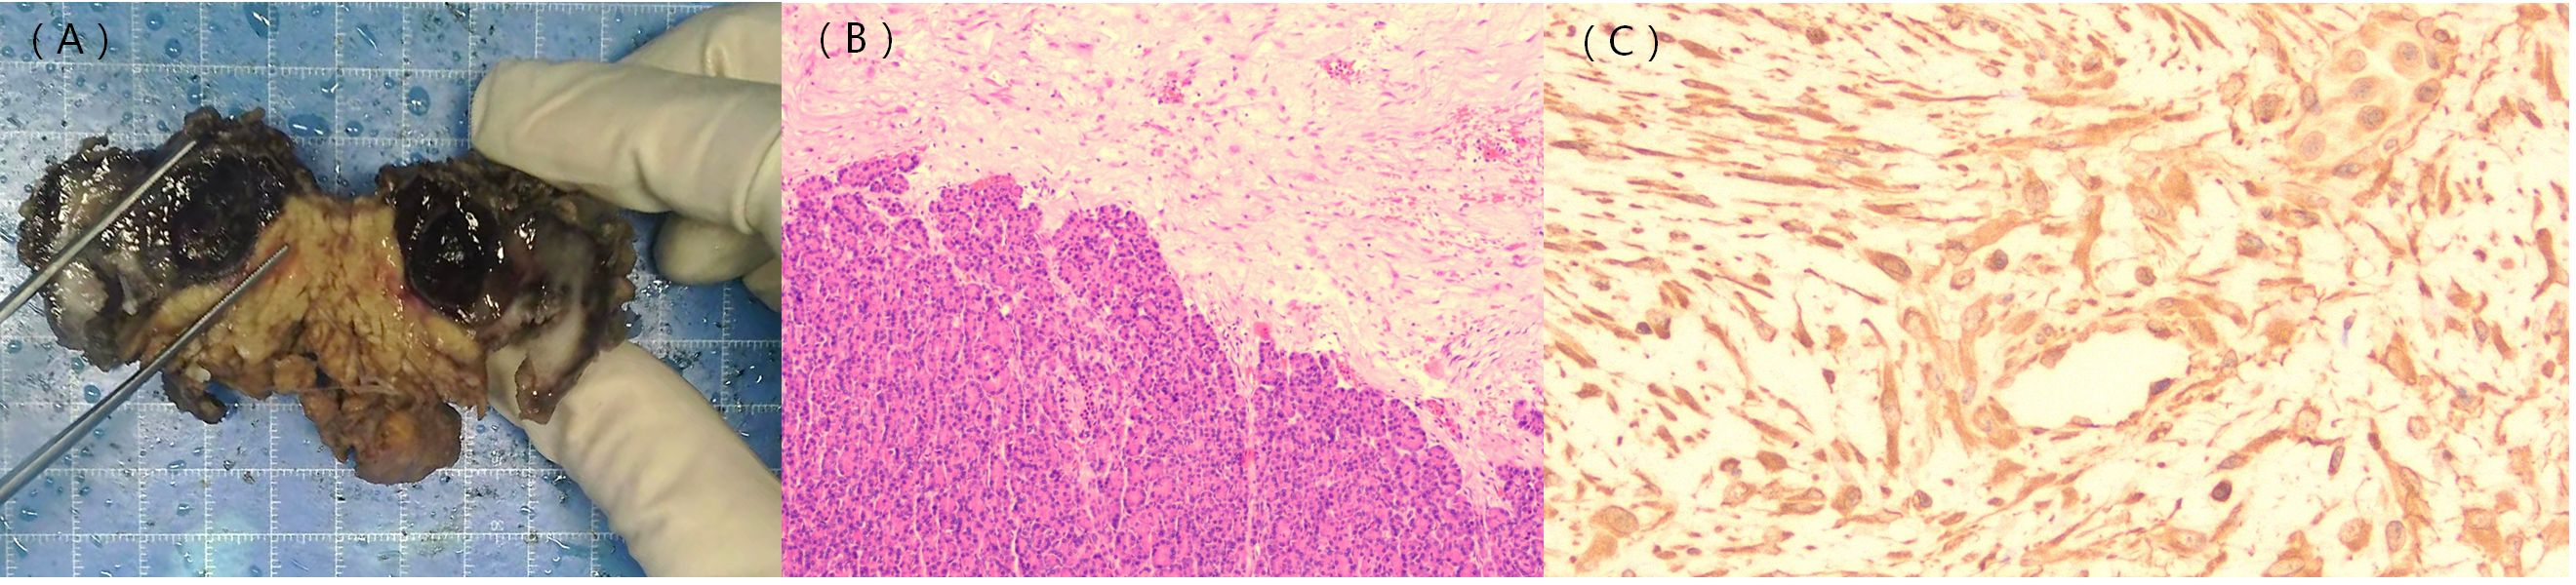

Figure 4

Panel (A) shows a gloved hand holding a bisected tissue specimen with dark areas. Panel (B) depicts a histological section with dense purple-stained cells. Panel (C) displays a histopathology slide with scattered brown-stained fibrous structures.

Figure 4. Gross pathology image; histological and immunohistochemical findings. The gross pathology image shows a solid cystic lesion (A). Hematoxylin–eosin staining indicates densely arranged tumor cells and normal pancreatic tissue (B). β-catenin staining shows positive signals in the nuclei of the tumor cells [(C), ×400].

The patient underwent a surgical operation after general anesthesia. During the operation, a tumor of approximately 5.0 cm in diameter was found in the pancreatic body near the tail. The tumor tightly adhered to the stomach and jejunum. The pancreatic and splenic vessels were carefully separated along Toldt’s gap, revealing that the tumor was firmly attached to the retroperitoneum, posterior to the stomach, and adjacent to the beginning of the jejunum. Additionally, the splenic vein was encased by the tumor, leading to regional portal hypertension and localized varicose veins. Following surgery, a histopathological examination confirmed the diagnosis of pancreatic aggressive atypical cystic fibromatosis. Immunohistochemical staining was positive for β-catenin (Figure 4), vimentin, P53, and Ki-67 (10%) and negative for CKAE1/AE3,CK8/18, CD56, CK7, CK19, Syn, CgA, NSE, ER, PR, α-Inhibin, M C5AC, MUC2, MUC6, CDX2, Dog-1, CD117, CD34, SMA, desmin, HMB-45, Melan-A, and S-100. The tumor exhibited a low mitotic count (​​1 to 2/10 high-power fields ​​) and a stromal composition characterized by a ​​collagen proportion of 20%.

The definitive diagnosis of AFP depends primarily on pathology and immunohistochemistry. Histopathological examination revealed that the tumors consist of varying proportions of spindle-forming fibroblasts and collagen fibers. Additionally, a significant majority (90%–95%) of the tumors exhibited point mutations in the β-catenin (CTNNB1) gene, with the positive expression of β-catenin serving as the primary diagnostic criterion for pancreatic fibromatosis. CTNNB1 is involved in the formation of the Wnt/β-catenin signaling pathway, which promotes the transcription of pro-proliferative and anti-apoptotic genes, thereby driving uncontrolled cellular proliferation and tumorigenesis (37). Absence of staining for cytokeratins (CKAE1/AE3, CK8/18, CK7, and CK19) effectively excludes carcinoma (38), including primary PDAC and its variants. Similarly, negativity for neuroendocrine markers (Syn, CgA, and CD56) excludes a pancreatic neuroendocrine tumor (39).​​ CD34 negativity​​ helps exclude a ​​solitary fibrous tumor (40). In this case, immunohistochemistry revealed β-catenin-positive expression alongside the pathological characteristics observed under the microscope. Combined with the negative results mentioned above, these collectively led to the definitive diagnosis of AFP and excluded all other major differential diagnoses. This case demonstrated a Ki-67 proliferative index of approximately 10%, which is inconsistent with the low indices (typically 1% to 2%) most commonly reported in the literature for AFP (3, 12, 17, 32). This discrepancy may reflect the atypical nature of this particular case and highlights the potential biological heterogeneity of this disease. The local invasiveness observed in our patient, as evidenced by the invasion into surrounding structures as seen on imaging and during surgery, may be associated with this higher proliferative activity (41). While diagnostic confirmation remains rooted in classic histology and β-catenin immunophenotype, the Ki-67 index could potentially serve as a supplementary indicator of a more aggressive clinical subtype. Further accumulation of cases with detailed long-term follow-up is necessary to determine whether a higher Ki-67 index correlates with a greater risk of recurrence or a more aggressive clinical course in AFP. The tumor exhibited a ​​low mitotic count (1 to 2/10 high-power fields)​​, which is characteristic of its biologically ​​benign nature (42). ​​Semi-quantitative assessment​​ revealed a ​​collagen proportion of approximately 20%​​, indicating a ​​highly cellular lesion​​ with a relatively scant collagenous stroma (43). This finding suggests a proliferative cellular state, which is consistent with the tumor’s ​​elevated Ki-67 proliferation index.